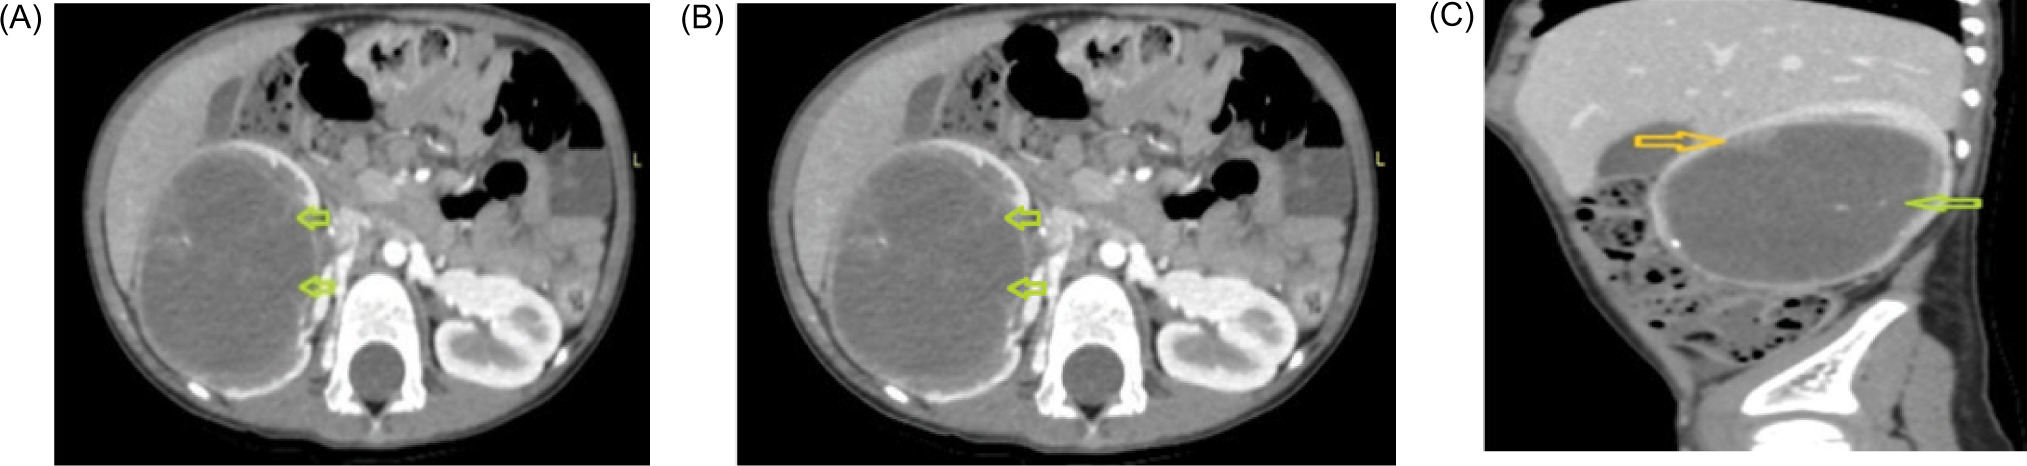

urinary vanillylmandelic acid (VMA) level was 0.4 mg/day (normal: 0–8). A computerized tomography scan (CT) revealed a large single complex cyst of size 8.6 x 6.3 x 6.1cm in the right kidney with enhancing septations, peripheral wall calcifications, and ill-defined soft tissue component within the cyst wall (BOSNIAK category IV) with few enlarged para-aortic nodes (Figure 1). CT scan of the chest was negative for metastasis. The fludeoxyglucose-18 (FDG) positron emission tomography (PET) scan revealed uptake only in the right kidney with no other sites of abnormal metabolic uptake. He underwent a right radical nephrectomy with retroperitoneal lymph node dissection (paracaval, precaval, and interaortocaval). Light microscopy revealed slender papillae with hyalinized fibrovascular cores, papillae lined by a single layer of uniform-looking epithelial cells with hyperchromatic nuclei, psammoma bodies, and necrosis (70%). Mitosis was scanty. Immunohistochemistry (IHC) showed positive reaction to transcription factor E3 (TEF3), keratin, vimentin, cytokeratin (CK-7), cluster of differentiation (CD10), and carbonic anhydrase-9, and negative reaction to alpha-methylacyl coenzyme-A racemase (AMACR), Epithelial membrane antigen (EMA), and variable Paired box gene (PAX-8) (Figure 2). KI-67 was 10–20%. The final histopathology was suggestive of translocation-associated RCC. All nodes were free (0/40). He was staged as pT2aN0. The patient had an uneventful postoperative recovery period and continues to be on regular follow-up with a disease-free survival of 36 months.

Figure 1: Contrast-enhanced CT scan (abdomen and pelvis). (A) Axial noncontrast images, showing a heterodense solid cystic mass in the right kidney, showing the presence of calcifications (yellow arrow). (B) and (C) Axial and sagittal CECT images showing a cystic lesion in the right kidney with thin enhancing internal septations (green arrow) and peripherally placed solid components (yellow arrow).